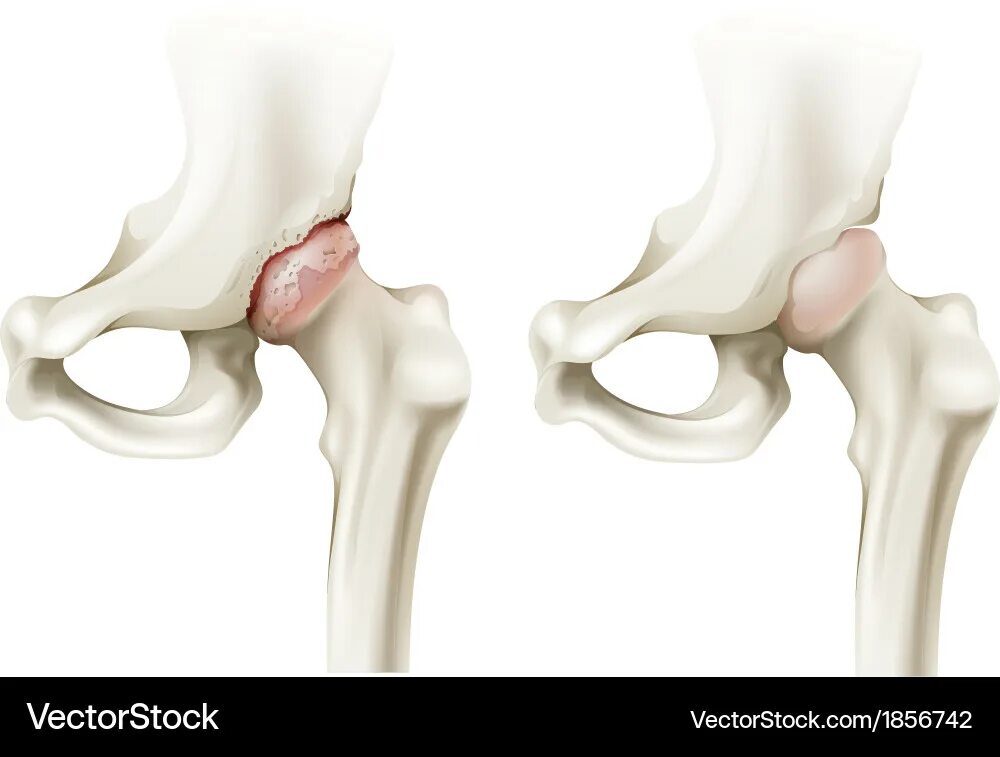

Доа тазобедренных суставов 1 степени что это